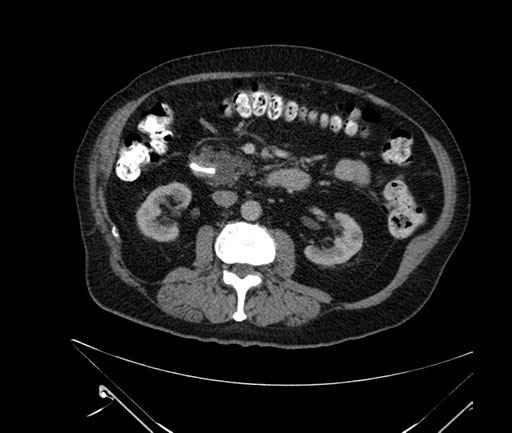

Imaging Analysis

Look through the patient's CT scan to identify any areas of concern for the necessary procedure.

Based on your CT findings, which issue(s) would give reason for "planned slowing down moment(s)" in this case?

Considering a standard Whipple procedure, what step(s) of the operation would you do differently in this case?